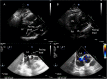

Inadvertent malposition of a pacemaker lead in the left ventricle is uncommon, but it should not be misdiagnosed. We report the case of a 68-year-old woman with symptomatic sick-sinus syndrome requiring pacemaker implantation. Shortly afterwards the lead was extracted and a new pacemaker was contralaterally implanted due to pocket hematoma and suspected lead fracture. Three months later, she was referred to our echocardiography laboratory complaining of asthenia. At transthoracic echocardiography an echo-bright linear structure was recognized in left atrium, passing through the mitral valve and leaning against the posterior left ventricular wall. In short-axis and apical views, the lead apparently crossed the interatrial septum through patent foramen ovale. The QRS-paced electrocardiogram showed right bundle branch block morphology. The lead was apparently well positioned, examining the chest X-ray postero-anterior view. On the contrary, by latero-lateral view and left-anterior oblique view, lead curvature was consistent with misplacement into the left ventricle. Malposition was confirmed by transesophageal echocardiography. Given the relatively recent implant, system revision with lead extraction was scheduled and completed without complications. This case report is intended to improve our awareness in the prevention and in the prompt detection of misplaced pacemaker leads in order to manage an immediate correction. <Learning objective: During lead implantation, fluoroscopic left-anterior oblique view should be always used to ensure correct positioning. At least 3-6 limb leads should be carefully monitored during the procedure, and a 12-lead standard electrocardiogram should be performed shortly afterwards for the paced QRS morphology. Lateral chest X-ray should always be taken after implantation. In cases of doubt, echocardiography (transthoracic or transesophageal) may confirm abnormal lead placement defining the route covered by the catheter.>.